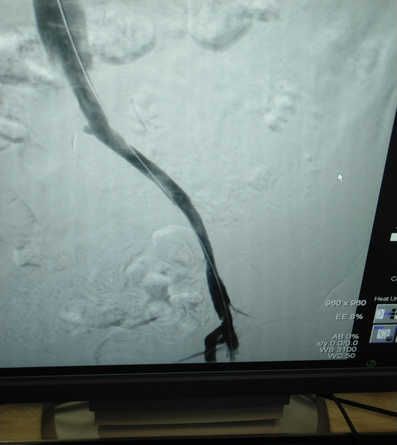

患者辛某,两月前左腿肿胀来我院就诊,B超检查发现左下肢深静脉血栓,经下腔静脉滤器植入术标准抗凝治疗后,患肢肿胀明显改善,两月后复查超声,左下肢深静脉内血栓基本消失,但左腿肿胀仍时轻时重。近期又在我院住院治疗,经左下肢顺行造影发现左侧髂静脉完全闭塞。经由交大一附院刘亚民教授会诊后,诊断为左侧髂静脉压迫综合症。

6月30日晚8时,在刘亚民教授的精心指导下,介入科李渊博主治医师与科室医护人员为该患者实施了血管开通、球囊扩张成形及支架置入术,术后造影,左侧髂静脉通畅,患者安全返回病房。